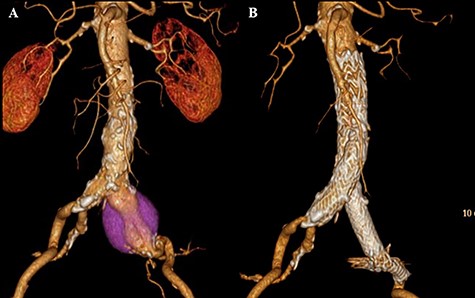

One year after open conversion, CT scan showing the significantly dilated infrarenal aorta (A) compared with the aorta before open repair (B).